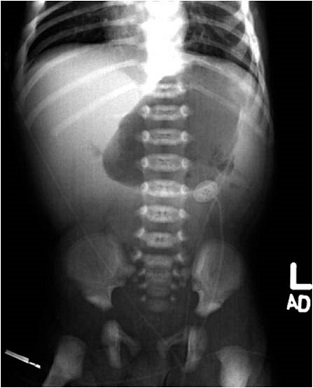

【112-1 醫學(五) 第48題】原本無異狀的10天大男嬰突然出現膽汁性嘔吐,影像學檢查如圖所示,最有可能的診斷是:

新生兒出現膽汁性嘔吐(bilious vomiting)是急症,必須立即評估是否有腸道阻塞或缺血。影像學檢查顯示胃部擴張,但腸道氣體分佈不典型,此時應高度懷疑最危險的診斷。